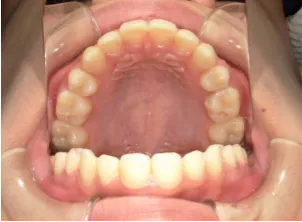

治療前①小2:8y1m 初診

治療中➁小3:9y8m QH、BH、前歯並び替え終了

治療後⑩高2:17y7m 抜歯治療終了

| カウンセリング・診断結果 | 前歯が受け口になっていているため、適正な成長へ誘導するために前歯の咬み合わせの改善が必要なことを説明し、診断を希望されたので精密検査へ進みました。 精密検査の結果、骨格的には受け口傾向、下顎前歯の突出、上下ともアーチが小さく凸凹(叢生)が認められ、機能的には低位舌と口唇閉鎖不全があり、口元は上下唇とも突出していますがコンケーブになってないことがわかりました。 |